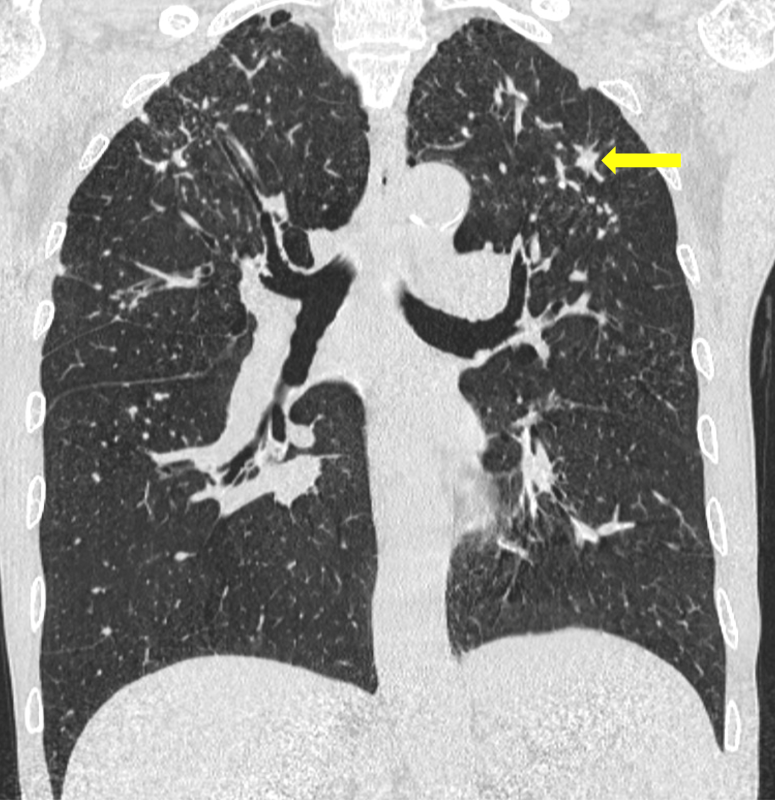

肺部高分辨率计算机断层扫描(HRCT)显示多个边界清晰的肺结节

,肺尖和周围易受累,肺底相对正常(图1和2)。结节的直径从约几毫米到一厘米不等,并显示散在钙化(图3)。在上叶这些结节显示出融合趋势;没有空洞形成。也有轻度肺气肿

以及弥漫性支气管壁增厚。患者最终诊断为Caplan综合征。

图2 冠状CT显示上叶肺结节,有融合趋势(箭头)。